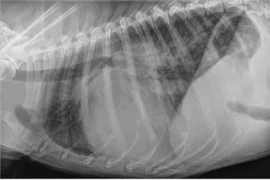

Interesting Radiographic Case Studies

Dr Catheryn has worked in general practice for 12 years. She received a membership in diagnostic imaging in 2018, has a special interest in internal medicine, and a graduate certificate in abdominal ultrasound. She is currently undertaking post graduate study in cardiology. She runs her own mobile ultrasound business and analyses radiographs for other vets on a regular basis.